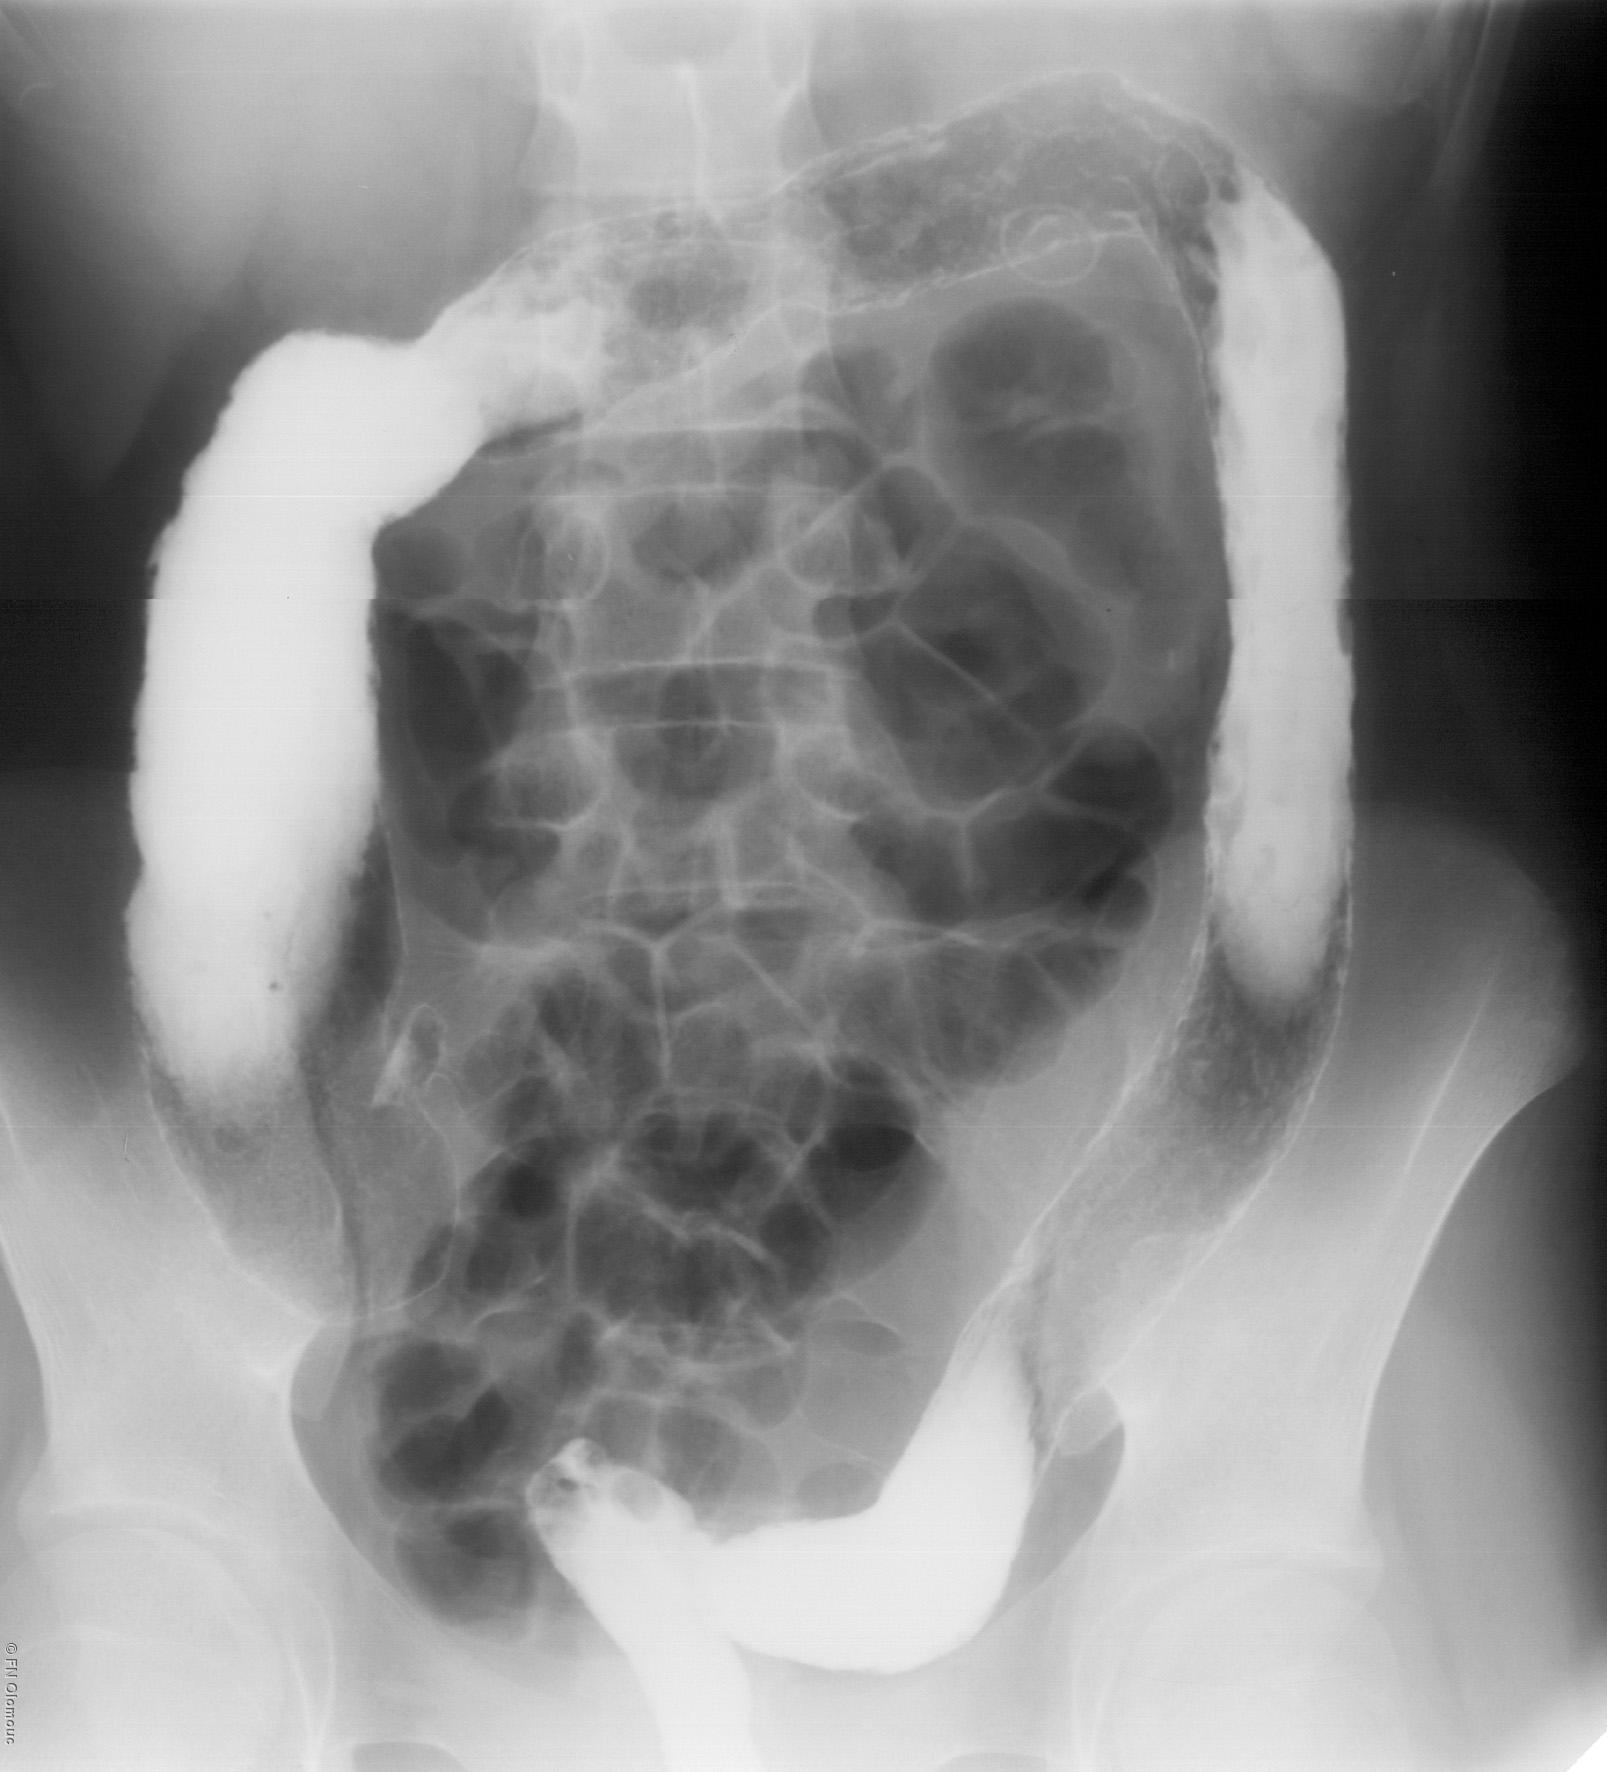

Výpočetní tomografieVýpočetní tomografie (CT - Computed Tomography) je zobrazovací metoda využívající digitální zpracování dat o průchodu rentgenového záření v mnoha průmětech vyšetřovanou vrstvou. Princip je stejný jako při klasickém snímkování - jde o zeslabení procházejícího rentgenového záření ve vyšetřovaném objektu. Svazek záření vycházející z rentgenky je vycloněn do tvaru vějíře, jehož šířka určuje šířku zobrazované vrstvy. Záření po průchodu vyšetřovaným objektem (pacientem) dopadá na detektory uložené naproti rentgence. Zde se množství dopadajícího záření převádí na elektrický signál, který dále zpracovává počítač. Během rotace jsou provedeny stovky měření, z nichž počítač rekonstruuje obraz vyšetřované vrstvy (je dán hodnotami absorpčních koeficientů z jednotlivých míst dané vyšetřované vrstvy).

CT snímek břicha.